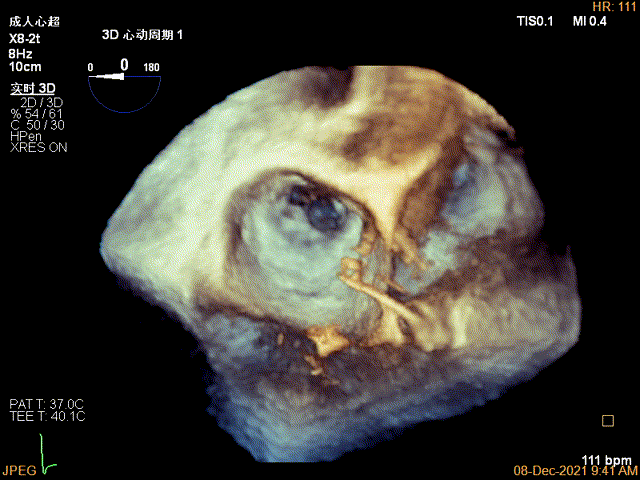

3D-VIEW验证结果

3D-Color-view验证残余分流位于外侧